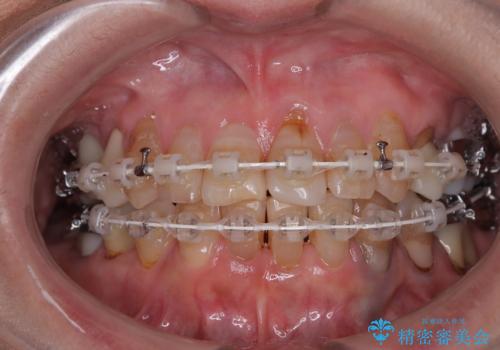

- 長年気にしていた捻れた前歯が欠けたとのことで来院された患者様です。

矯正治療に抵抗があったそうですが、前歯が欠けたことをきっかけに、矯正治療で歯列を整えた上で、セラミッククラウン治療を行う決心が付いたとのことでした。

デコボコが強いため、ブリッジや残根となっている部分のスペースを利用して歯列を整え、変色や欠けている歯をオールセラミッククラウンによる補綴治療を行うこととしました。